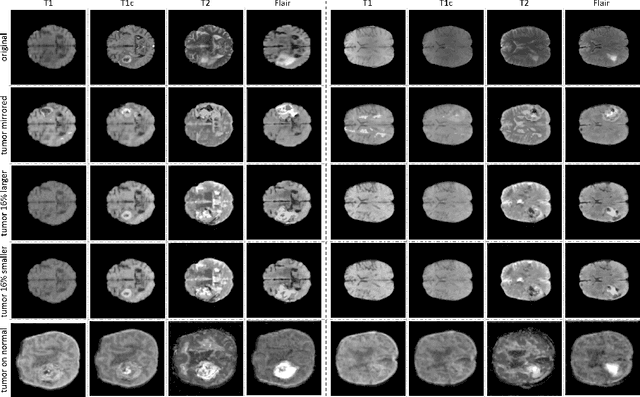

Abstract:Data diversity is critical to success when training deep learning models. Medical imaging data sets are often imbalanced as pathologic findings are generally rare, which introduces significant challenges when training deep learning models. In this work, we propose a method to generate synthetic abnormal MRI images with brain tumors by training a generative adversarial network using two publicly available data sets of brain MRI. We demonstrate two unique benefits that the synthetic images provide. First, we illustrate improved performance on tumor segmentation by leveraging the synthetic images as a form of data augmentation. Second, we demonstrate the value of generative models as an anonymization tool, achieving comparable tumor segmentation results when trained on the synthetic data versus when trained on real subject data. Together, these results offer a potential solution to two of the largest challenges facing machine learning in medical imaging, namely the small incidence of pathological findings, and the restrictions around sharing of patient data.